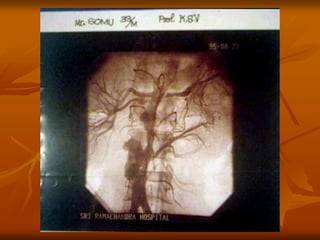

SUBCLAVIAN- AXILLARY ANEURYSM

 POST STENOTIC DILATATION--- OUTLET OBSTRUCTION

 Younger patients/females/ right side more common

 Associated with CERVICAL RIBS

 Associated with Raynauds phenomenon.

 ARTERIOGRAPHY – To assess the degree of post

 stenotic dilation of the subclavian artery.

 Rx—significant dilation– CERVICAL RIB removal

 vascular reconstruction– mobilization with end

to end anastomosis with or without short

interposition vein or prosthetic graft.